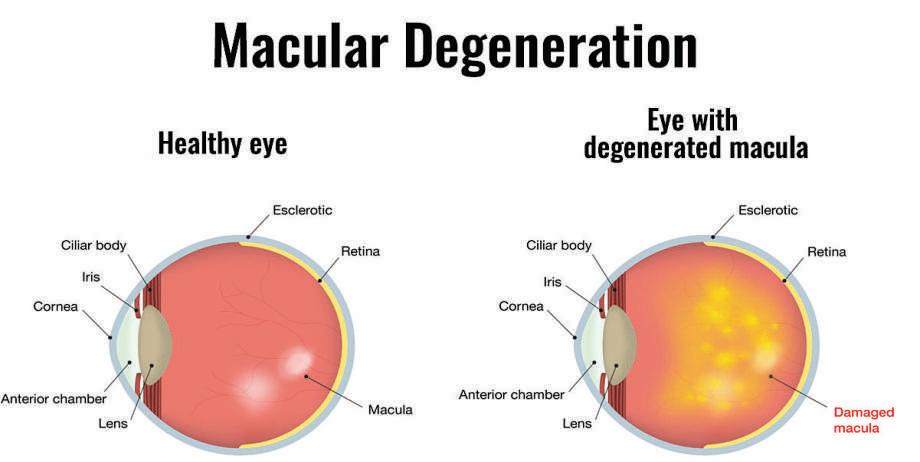

OneinSevenpeople over50willget Macular Degeneration

MD is theleading causeofseverevisionloss. 1in7 people over the ageof50years isaffectedinsome wayand theincidence increases with age. 1in4peopleoverthe ageof80havesomevisionloss.

WhatisMacularDegeneration(MD)?

Themaculaisthecentralpartoftheretina, thelightsensitivetissueatthebackoftheeye. Theretinaprocessesallvisualimages.Itis responsibleforyourabilitytoread,recognise faces,driveandseecoloursclearly.Youare readingthisusingyourmacula.Macular Degeneration(MD)causesprogressiveloss ofcentralvisionbutperipheralvisionisnot affected.

WhatarethetypesofMD?

TherearetwotypesofMD,dryandwet.DryMD resultsinagraduallossofcentralvision.Wet MDischaracterisedbyasuddenlossofvision causedbyabnormalbloodvesselsgrowing undertheretina.Immediatemedicaltreatment ofwetMDisessentialifsymptomsoccur.

Whataretheriskfactors?

Asidefromincreasingageover50years, MDisthoughttobecausedbygeneticand environmental afamilyhis thediseaseis includedie

HowcanyoutellifyouhaveMD?

Symptomsmayincludeoneormoreofthefollowing:

•Distortion,wherestraightlinesappearwavyorbent

•Difficultyreadingorotheractivitiesthatrequirefinevision

•Distinguishingfacesbecomesaproblem

•Darkpatchesoremptyspacesappearinthecentreofyourvision

•Poornightvision

•Decreasedcoloursensitivity

MacularDegenerationEyehealthchecklist

•Haveyoureyestestedandmakesurethemaculaischecked.

•Don'tsmoke.

•Keepahealthylifestyle,controlyourweightandexerciseregularly.

•Eatahealthy,well-balanceddiet.Limityourintakeoffats,eatfishtwoor threetimesaweek,eatdarkgreenleafyvegetablesandfreshfruitdaily andahandfulofnutsaweek.

•Inconsultationwithyourdoctor,considertakingazincandantioxidant supplement.

•Provideadequateprotectionforyoureyesfromsunlightexposure, especiallywhenyoung.

Amslergrid

TheAmslergridmaybeusedtodetectdistortioninvisionwherestraight linesappearwavyorbentandtoseeiftherearedarkspacesorempty patchesinthevision.Gotohttp://mdnz.org.nzforanamslergridand furtherinformationonMaculaDegeneration